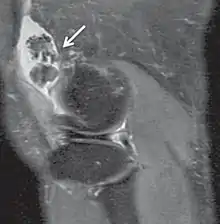

| كثافة البروتون | PD | وقت التكرار الطويل ووقت الصدى القصير.[4] | جرح واعتلال المفاصل.[5]

|

كثافة البروتون

تُجمع الصور الموزونة بكثافة البروتون من خلال وقت التكرار الطويل ووقت الصدى القصير،[31] وهذا الوزن يُعطي تمييز أكثر وضوحًا بين المادة الرمادية (الساطعة) والمادة البيضاء (الرمادي الداكن) في صور الدماغ، ولكن مع تباين ضئيل بين الدماغ و السائل الدماغي الشوكي. ويُعتبر هذا الوزن مفيد جدًا في الكشف عن أمراض المفاصل وإصاباتها.[32]